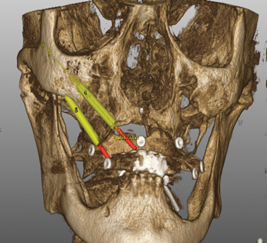

Treatment options for full-arch restorations include the placement of conventional implants in the anterior region accompanied by single zygomatic implants in the posterior left and right (Figure 1),48 the classic "quad zygoma" concept with four zygomatic implants in position (Figure 2),19,49 and the pterygoid fixated arch stabilization technique, which combines two anterior conventional implants, two zygomatic implants, and two pterygoid implants (Figure 3).50 Treatment plans can now be customized to optimize the implant positions based on each patient's anatomy and needs.

(2.) Treatment planning view of the implant positions in a quad zygoma case.

Figure 2